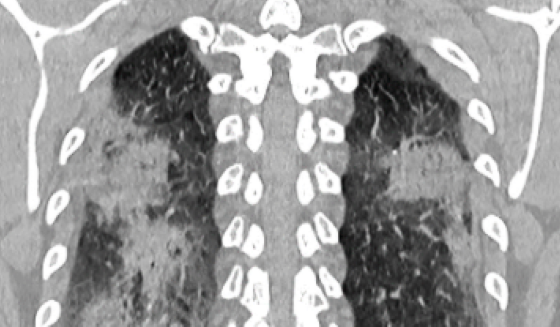

(RSNA) – CT Chest coronal view demonstrates multifocal nodular and mass-like airspace opacities in both lungs. Source: Song et al, Radiology 2020